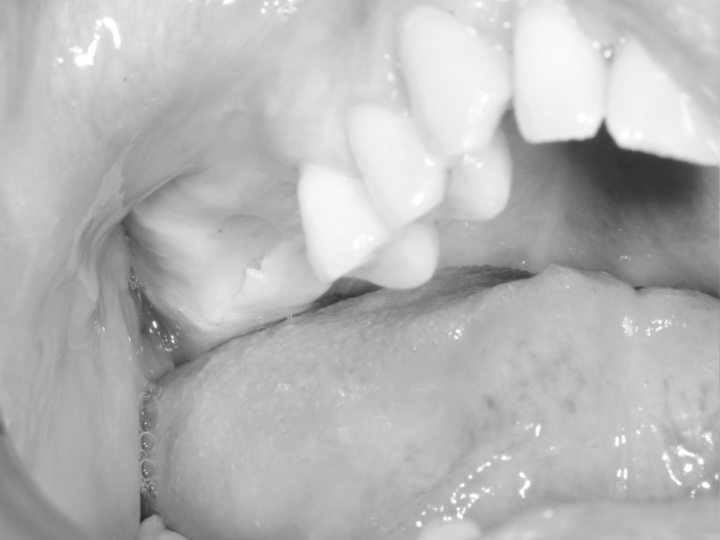

L’élévation sinusienne, également appelée sinus lift, est une intervention chirurgicale visant à augmenter le volume osseux dans la région postérieure du maxillaire supérieur. Elle peut être envisagée lors de la planification de certains traitements restaurateurs, notamment lorsque le volume osseux disponible est insuffisant.

Lorsque le volume osseux a diminué à la suite d’une perte dentaire ou d’une maladie parodontale, l’élévation sinusienne consiste à déplacer le plancher du sinus afin de créer un espace destiné à recevoir un matériau de greffe osseuse. Cette procédure vise à soutenir une hauteur osseuse suffisante, pouvant être prise en compte lors de l’évaluation des options restauratrices.